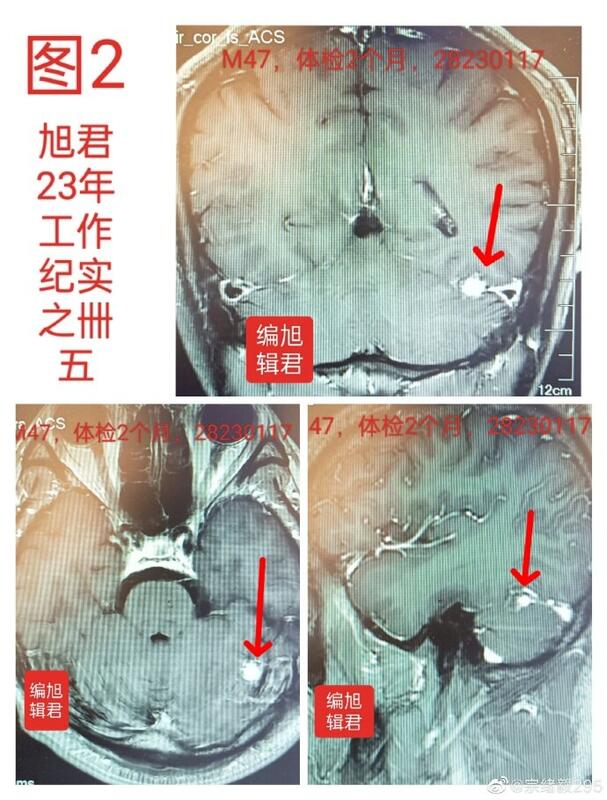

图2:某患者47岁,体检发现小脑膜瘤,无不适。

图-2